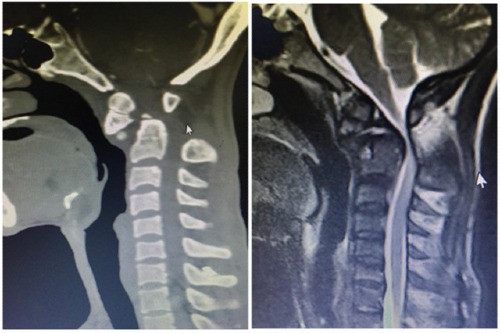

| Hình ảnh chụp CT trước khi mổ. Ảnh: BVCC |

Kết quả chụp cộng hưởng cho thấy bệnh nhân bị mất vững đốt sống cổ C1- C2 do gãy mỏm nha, bị chèn ép tủy sống ngang mức đốt sống C1, C2. Theo các bác sĩ, đây là trường hợp khá phức tạp bởi tổn thương đã kéo dài nhiều năm, nặng, nguy cơ khó hồi phục.